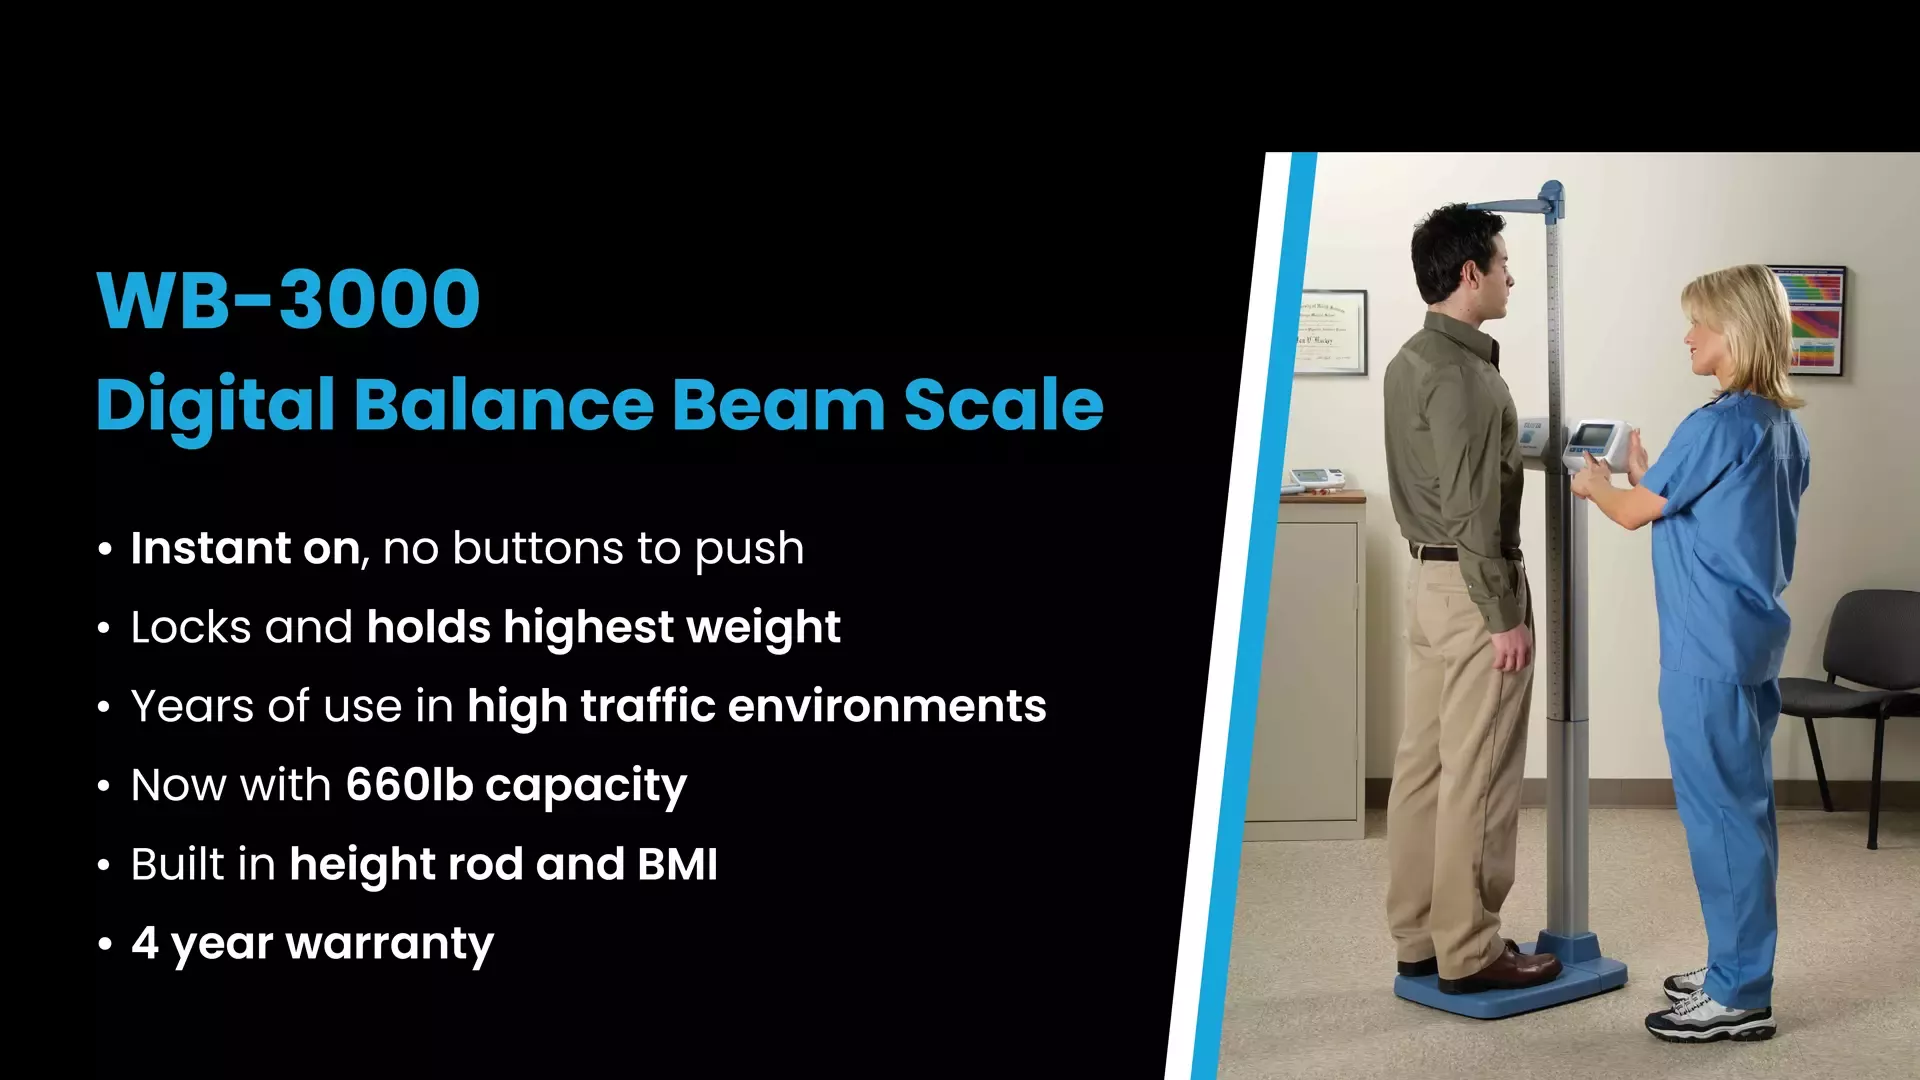

Professional Scales

Tanita's line of US Food & Drug Administration (FDA) approved professional scales incorporate state-of-the-art #technology within the most user-friendly package in the industry. Our Legal for Trade professional product line provides invaluable information to: clinical researchers #and medical experts, point-of-care physicians in the Acute Care, Long-Term Care, Pediatric and Veterinary practices, sports

coaches (wrestling, #training rooms), #and scientists working in the fields of obesity, cardiology, physiology, diabetes, nutrition, chiropractic, and rehabilitation therapies. These monitors and doctor scales, physician scales also help doctors by improving patient understanding and compliance in treatment programs and provide greater accessibility for patients, as well as, increased portability and accuracy

for healthcare professionals in the geriatric and bariatric fields.

Tanita's wide variety of professional analyzers provide a detailed full body and segmental body composition analysis - weight, impedance, body fat percentage, body fat mass, body mass index (BMI), fat free mass, estimated muscle mass, total body water, and basal metabolic rate (BMR) for the entire body by using Bioelectrical Impedance Analysis (BIA) or Direct-Segmental Bioelectrical Impedance Analysis (DSM-BIA) technology (two of the most thorough and reliable ways to measure body

composition). All scales are built with Tanita's high standards, and many products feature a convenient carrying case, height rod, USB (Type B) & RS232 outputs, software, and a remote display, guaranteeing #long-lasting performance, even in the most demanding healthcare environments.

Tanita's best-selling professional line #of high-capacity scales include pediatric/pediatrician (baby, neonatal) scales, physician scale, hospital scales, digital column scales, wheelchair scales, handrail and beam scales, NTEP scales, food/restaurant scales and a collection of laboratory scales. The lab scales are used for a #variety of diagnostic measurements, including hypertension, metabolic syndrome,

childhood obesity, and visceral fat detection used to identify bariatric surgery cases and those who may be at a higher risk for cancer.

As the world-leader in providing scales for healthcare professionals, Tanita scales are more affordable and convenient than DEXA (dual energy X-ray absorptiometry) or hydrostatic weighting, yet offer accuracy used in measuring multiple frequency BIA. Our scales provide insight into such indicators as weight loss, caloric intake, diet and #exercise, adipose tissue, and total body water (intracellular and extracellular water) in both pounds and kilograms

- making them useful for fitness gyms and clubs as well. #Some models feature stadiometers (height rods), are EMR compatible, are Welch Allen compatible, and wireless output, but all are ISO 9001 certified. TANITA is the only scale trusted by the NCAA Wrestling Championships, USA Wrestling, the Midlands Wrestling Championships, the Reno Tournament of Champions, the Dan #Gable

International Wrestling Institute #and Museum as well as countless other tournaments, programs and organizations worldwide